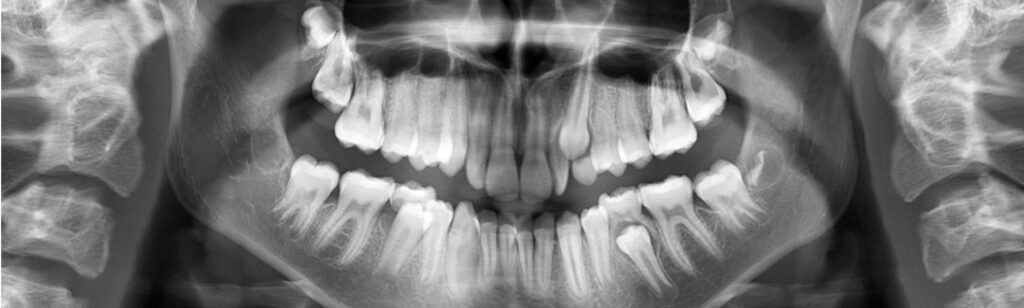

The 14-year-old female patient visited the orthodontic practice in February 2021. The chief complaint was that her upper arch was affecting her confidence in her smile. Upon examination, the patient was found to have a normodivergent facial pattern and a skeletal class II with mandibular retrusion. An intraoral examination revealed narrow arches, a class II molar and canine relationship, deep bite, retroclined upper and lower incisors, and retained teeth 63, 74, and 84.

After undergoing maxillary expansion, Dr. Sorina Blaj assessed the patient again in September 2021, and at that point, tooth 84 had exfoliated, tooth 44 had erupted, and tooth 23 had started to erupt.

The treatment includes sequential distalization of the maxillary teeth and mesialization of 3.6, virtual extraction of 74, composite attachments on all distalizing teeth, class II elastics, bite ramps on upper central incisors, IPR and eruption guides for teeth 23 and 35.